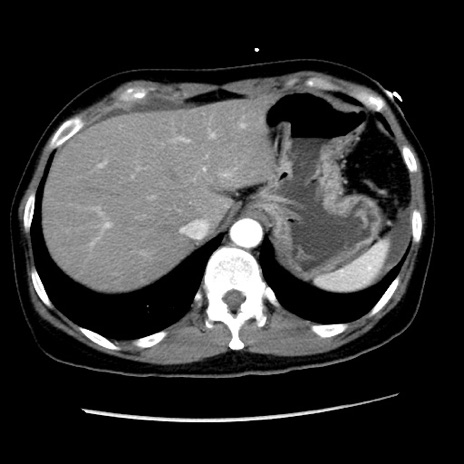

矢状断像

【症例】 50歳代女性

【主訴】 腹痛

【現病歴】前日生レバーを食べた。今朝に排便あり。 昼前に突然発症の腹痛を生じ、当院救急外来を受診した。

【既往歴】 子宮筋腫にてで子宮全摘後

【身体所見】 意識清明、腹部:平坦、軟、下腹部やや左を中心に圧痛・反跳痛あり、筋性防御あり

【データ】WBC 7800、CRP 0.07